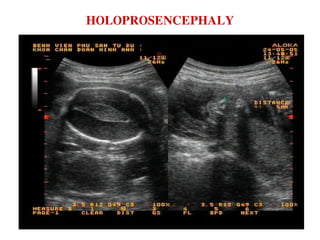

HOLOPROSENCEPHALY